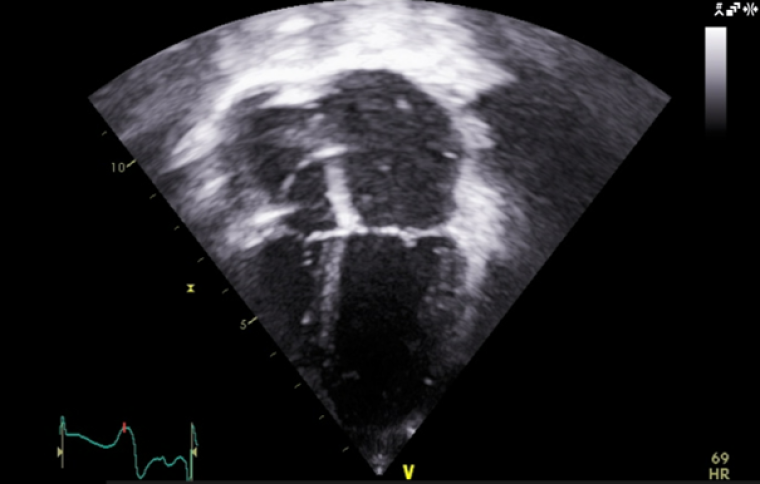

At the age of 4 years, the patient started developing a distinct echocardiographic phenotype (Image 5), with a dilated left atrium (LA) (LA area 12.1 cm3, z score +5.7) and right atrium (RA) (RA area 10.8 cm3, z score +4.1), preserved global left ventricular systolic function, but impaired longitudinal function (tissue doppler lateral S’ wave 0.07m/s, septal 0.05m/s) and evidence of early impaired left ventricular relaxation (isovolumetric relaxation time 114ms, pulmonary vein A-wave duration 166msm abnormal mitral valve doppler). The left ventricle itself was normal in size, with a maximal wall thickness of 5-6mm (z score +02), with no significant valvular or other abnormalities.

CC Vol 10 Picture5_escardio-Clinical case.png

The patient is now 11 years old. He is seen locally as well as by our service, and remains on 2mg/kg/day of nadolol with no further documented arrhythmic events. He is mainly paced in the atrium (99.7%) from his device. His ECG (Image 6) and echocardiogram (Image 7) remains stable.

CC Vol 10 Picture7_escardio-Clinical case.png